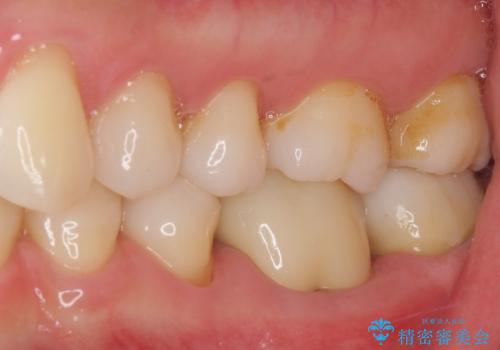

術後6ヶ月でレントゲン写真を撮影したところ、出血の原因であった穴付近の溶けていた骨が回復している様子が認められました。